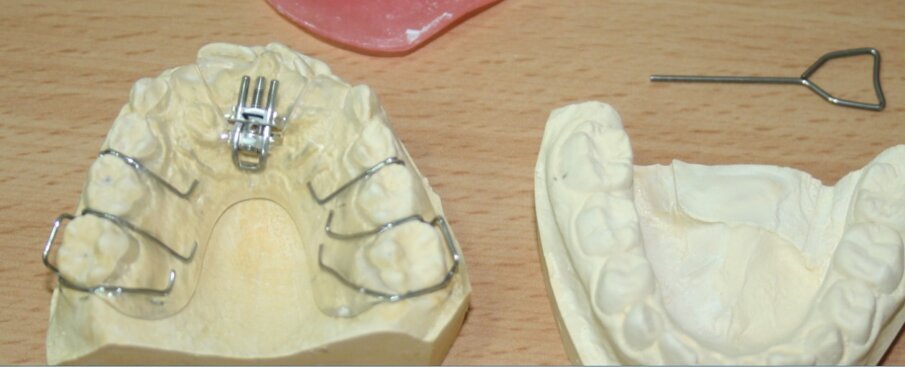

Fig. 13. Upper removable orthodontic appliance with an anterior expanding palatal screw; to correct the cross bite of 11 & 21. The expansion key is on the right

Upper and lower alginate impressions were taken (with difficulty due to LT’s gag reflex) to fabricate an upper removable anterior segment palatal expansion appliance (with an anterior expanding screw) and posterior bite blocks to correct the anterior cross bite (Fig. 13).